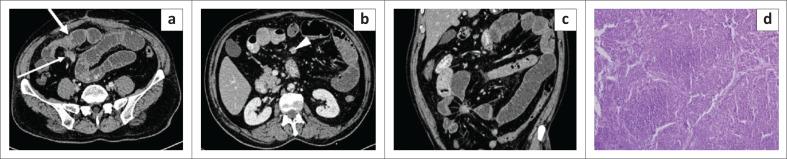

The mesentery is a broad fan-shaped fold of peritoneum that suspends the loops of small intestine from the posterior abdominal wall. Although primary neoplasms arising in the mesentery are rare, the mesentery is a major avenue for the dissemination of tumours, which can spread through hematogenous, lymphatic, direct or peritoneal seeding. Imaging helps in the diagnosis of these tumours and aids in directing appropriate treatment by assessing their size, extent and relationship with adjacent structures. The aim of this article is to describe the spectrum of imaging findings of the various mesenteric lesions using ultrasound and CT.

肠系膜是腹膜的一个宽阔扇形褶皱,将小肠袢从腹后壁悬吊起来。虽然起源于肠系膜的原发性肿瘤很少见,但肠系膜是肿瘤播散的主要途径,肿瘤可通过血行、淋巴、直接蔓延或腹膜种植扩散。影像学有助于这些肿瘤的诊断,并通过评估其大小、范围以及与相邻结构的关系来指导适当的治疗。本文旨在描述使用超声和CT对各种肠系膜病变的影像学表现范围。